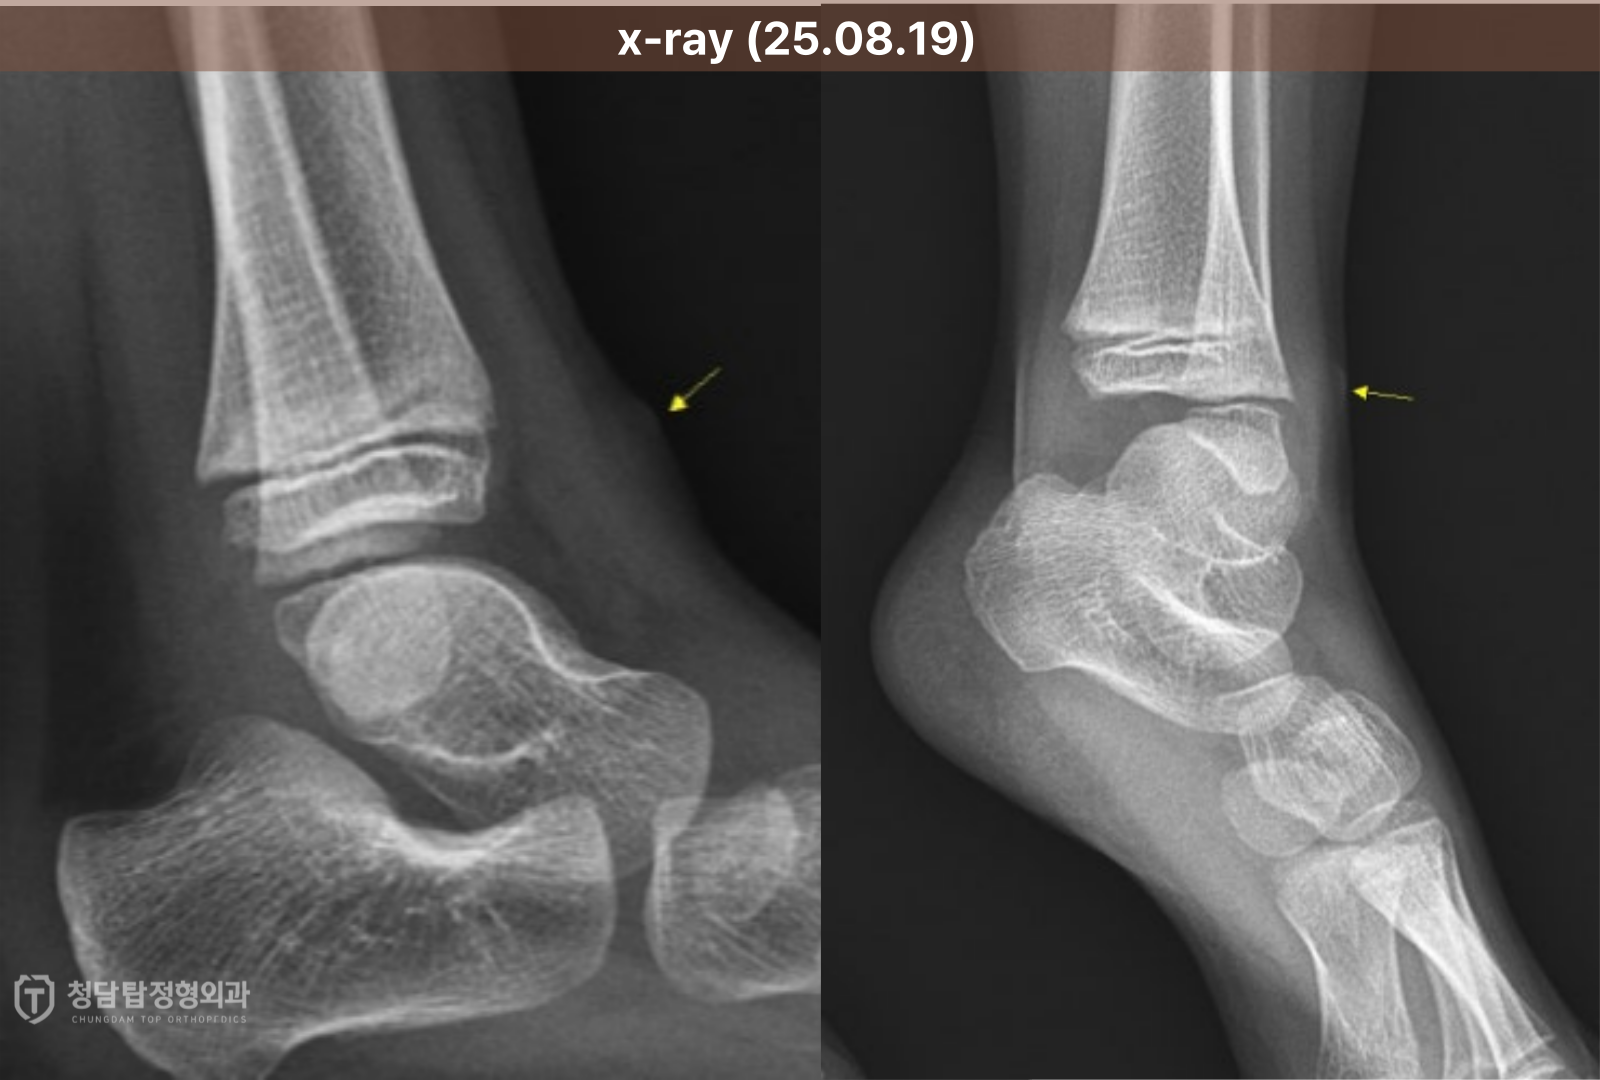

나무 가시는 X-ray로 확인이 어려워서

정확한 진단을 위해 곧바로 정밀 초음파 검사로 확인해봤습니다.